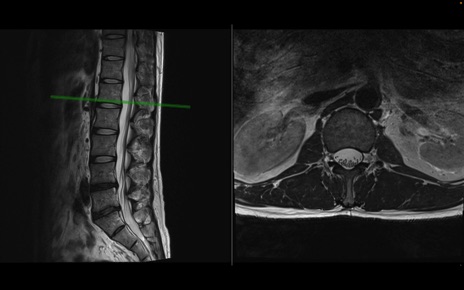

【整形】TIPS症例1 腰椎MRI 横断像と矢状断像

【症例】40歳代男性

【主訴】左臀部〜大腿後面痛み

【現病歴】2週間前から腰痛あり。2日前に夜中にくしゃみをした際に激痛が出現。疼痛強いため来院。

【身体所見】左臀部〜大腿後面、下腿後面のしびれ。SLR -/+ 30度、うつ伏せ困難、筋力低下なし。

異常所見と診断は?